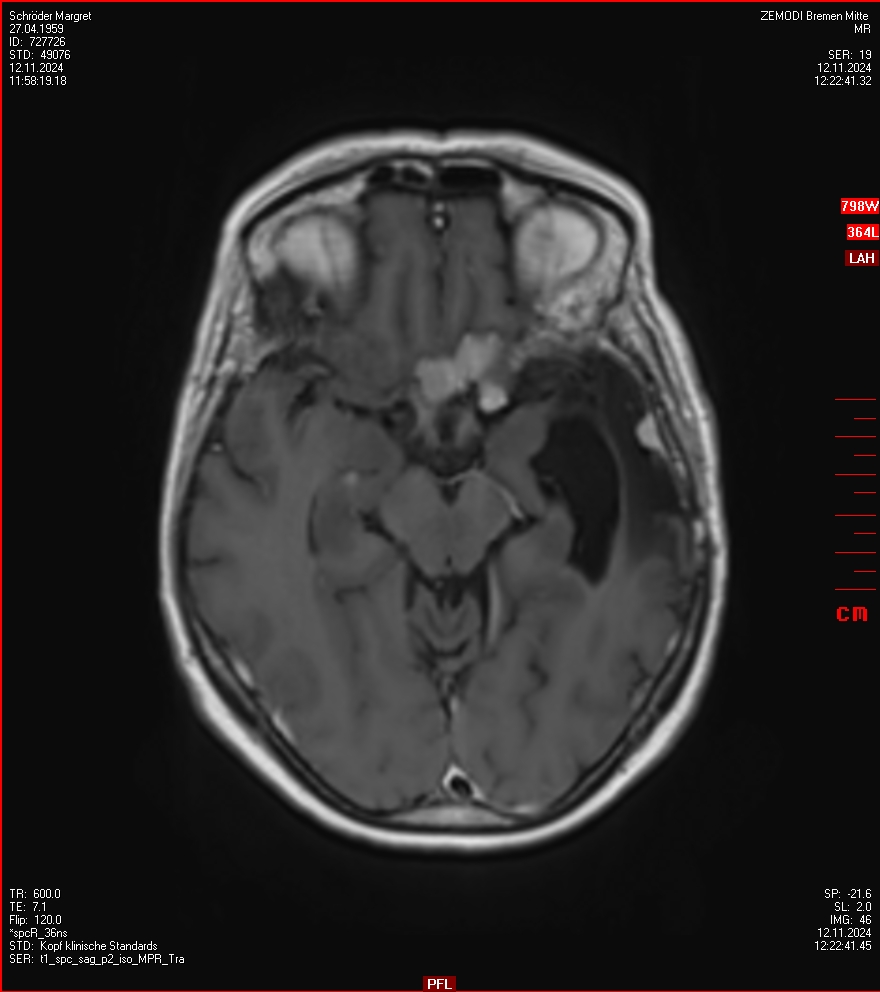

MRT vom 12. November 2024

So nun ein paar neue Bilder aus meinem Kopf. (Durch klicken bekommt man eine größe Ansicht eines Einzelbildes).

Die letzten drei Bilder Zeigen aus meiner Sicht den Tumor, der im Jahr 2021 bestrahlt wurde.

Ich denke, in den letzen 12 Monaten sind da ein paar Rezidive gewachsen,  vor 12 Monaten waren sie auch schon zu erkennen - vorher noch nicht. Nun hoffe ich auf den Rat des Spezialisten. Hoffendlich kann man etwas machen.